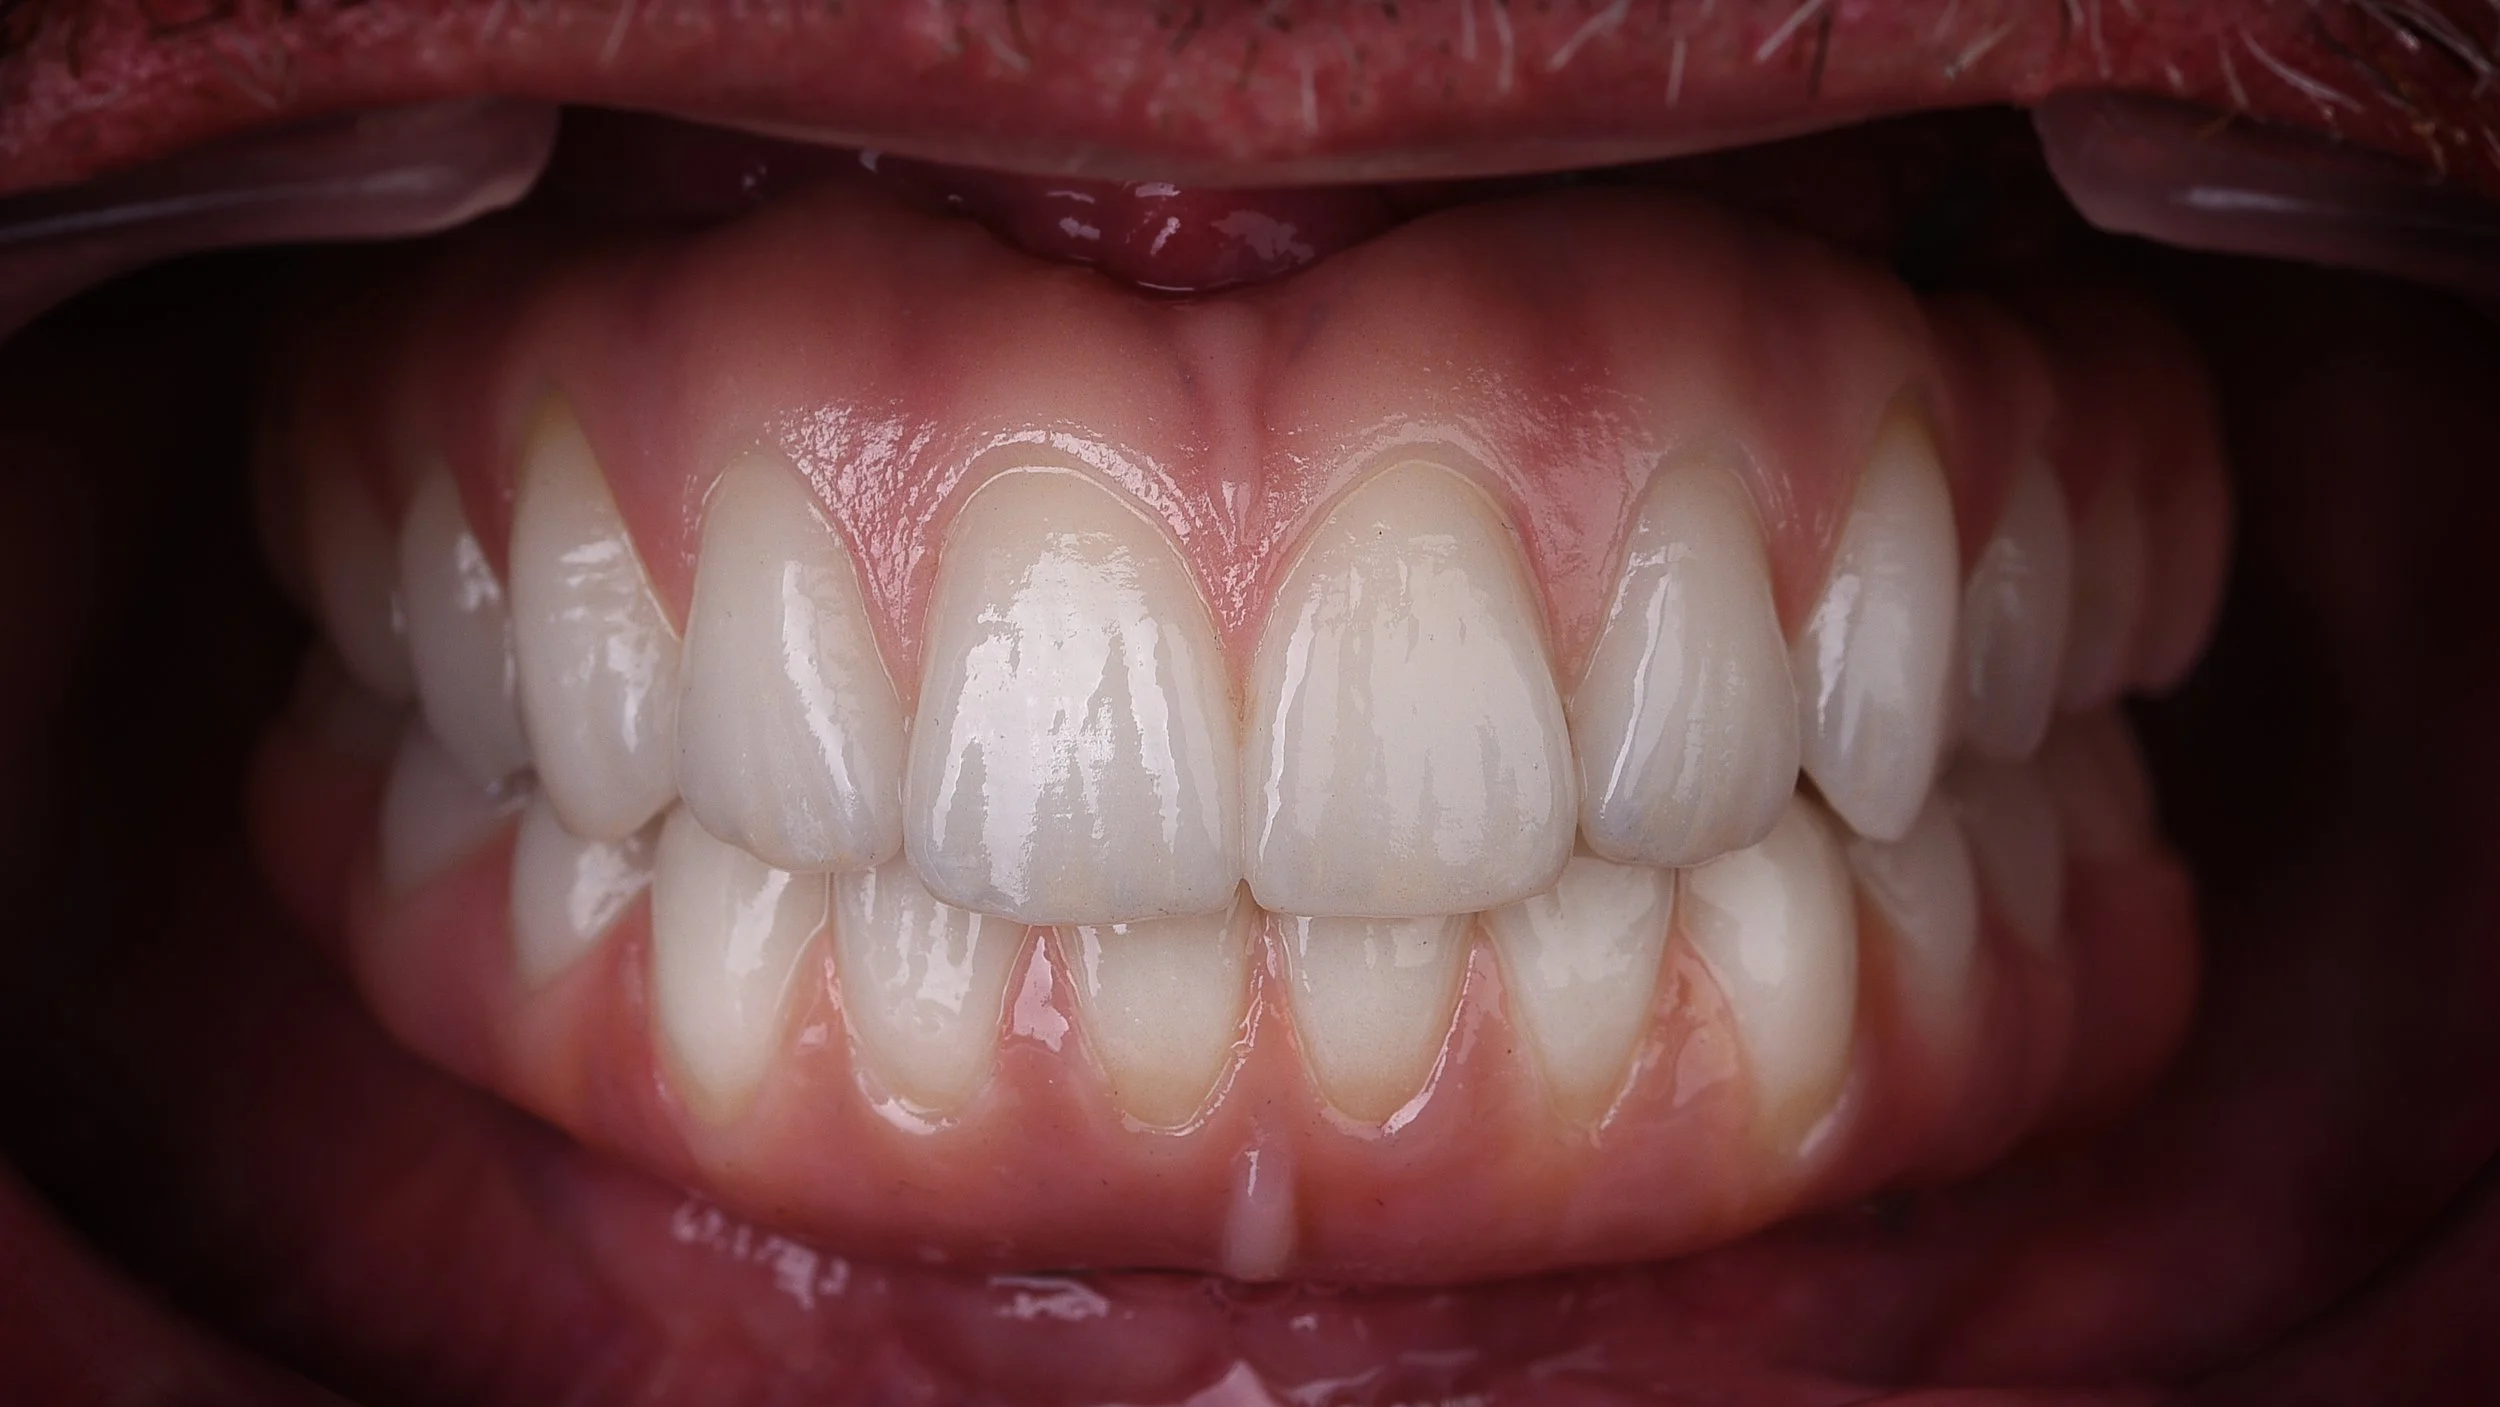

Rehabilitación completa con implates full Arch